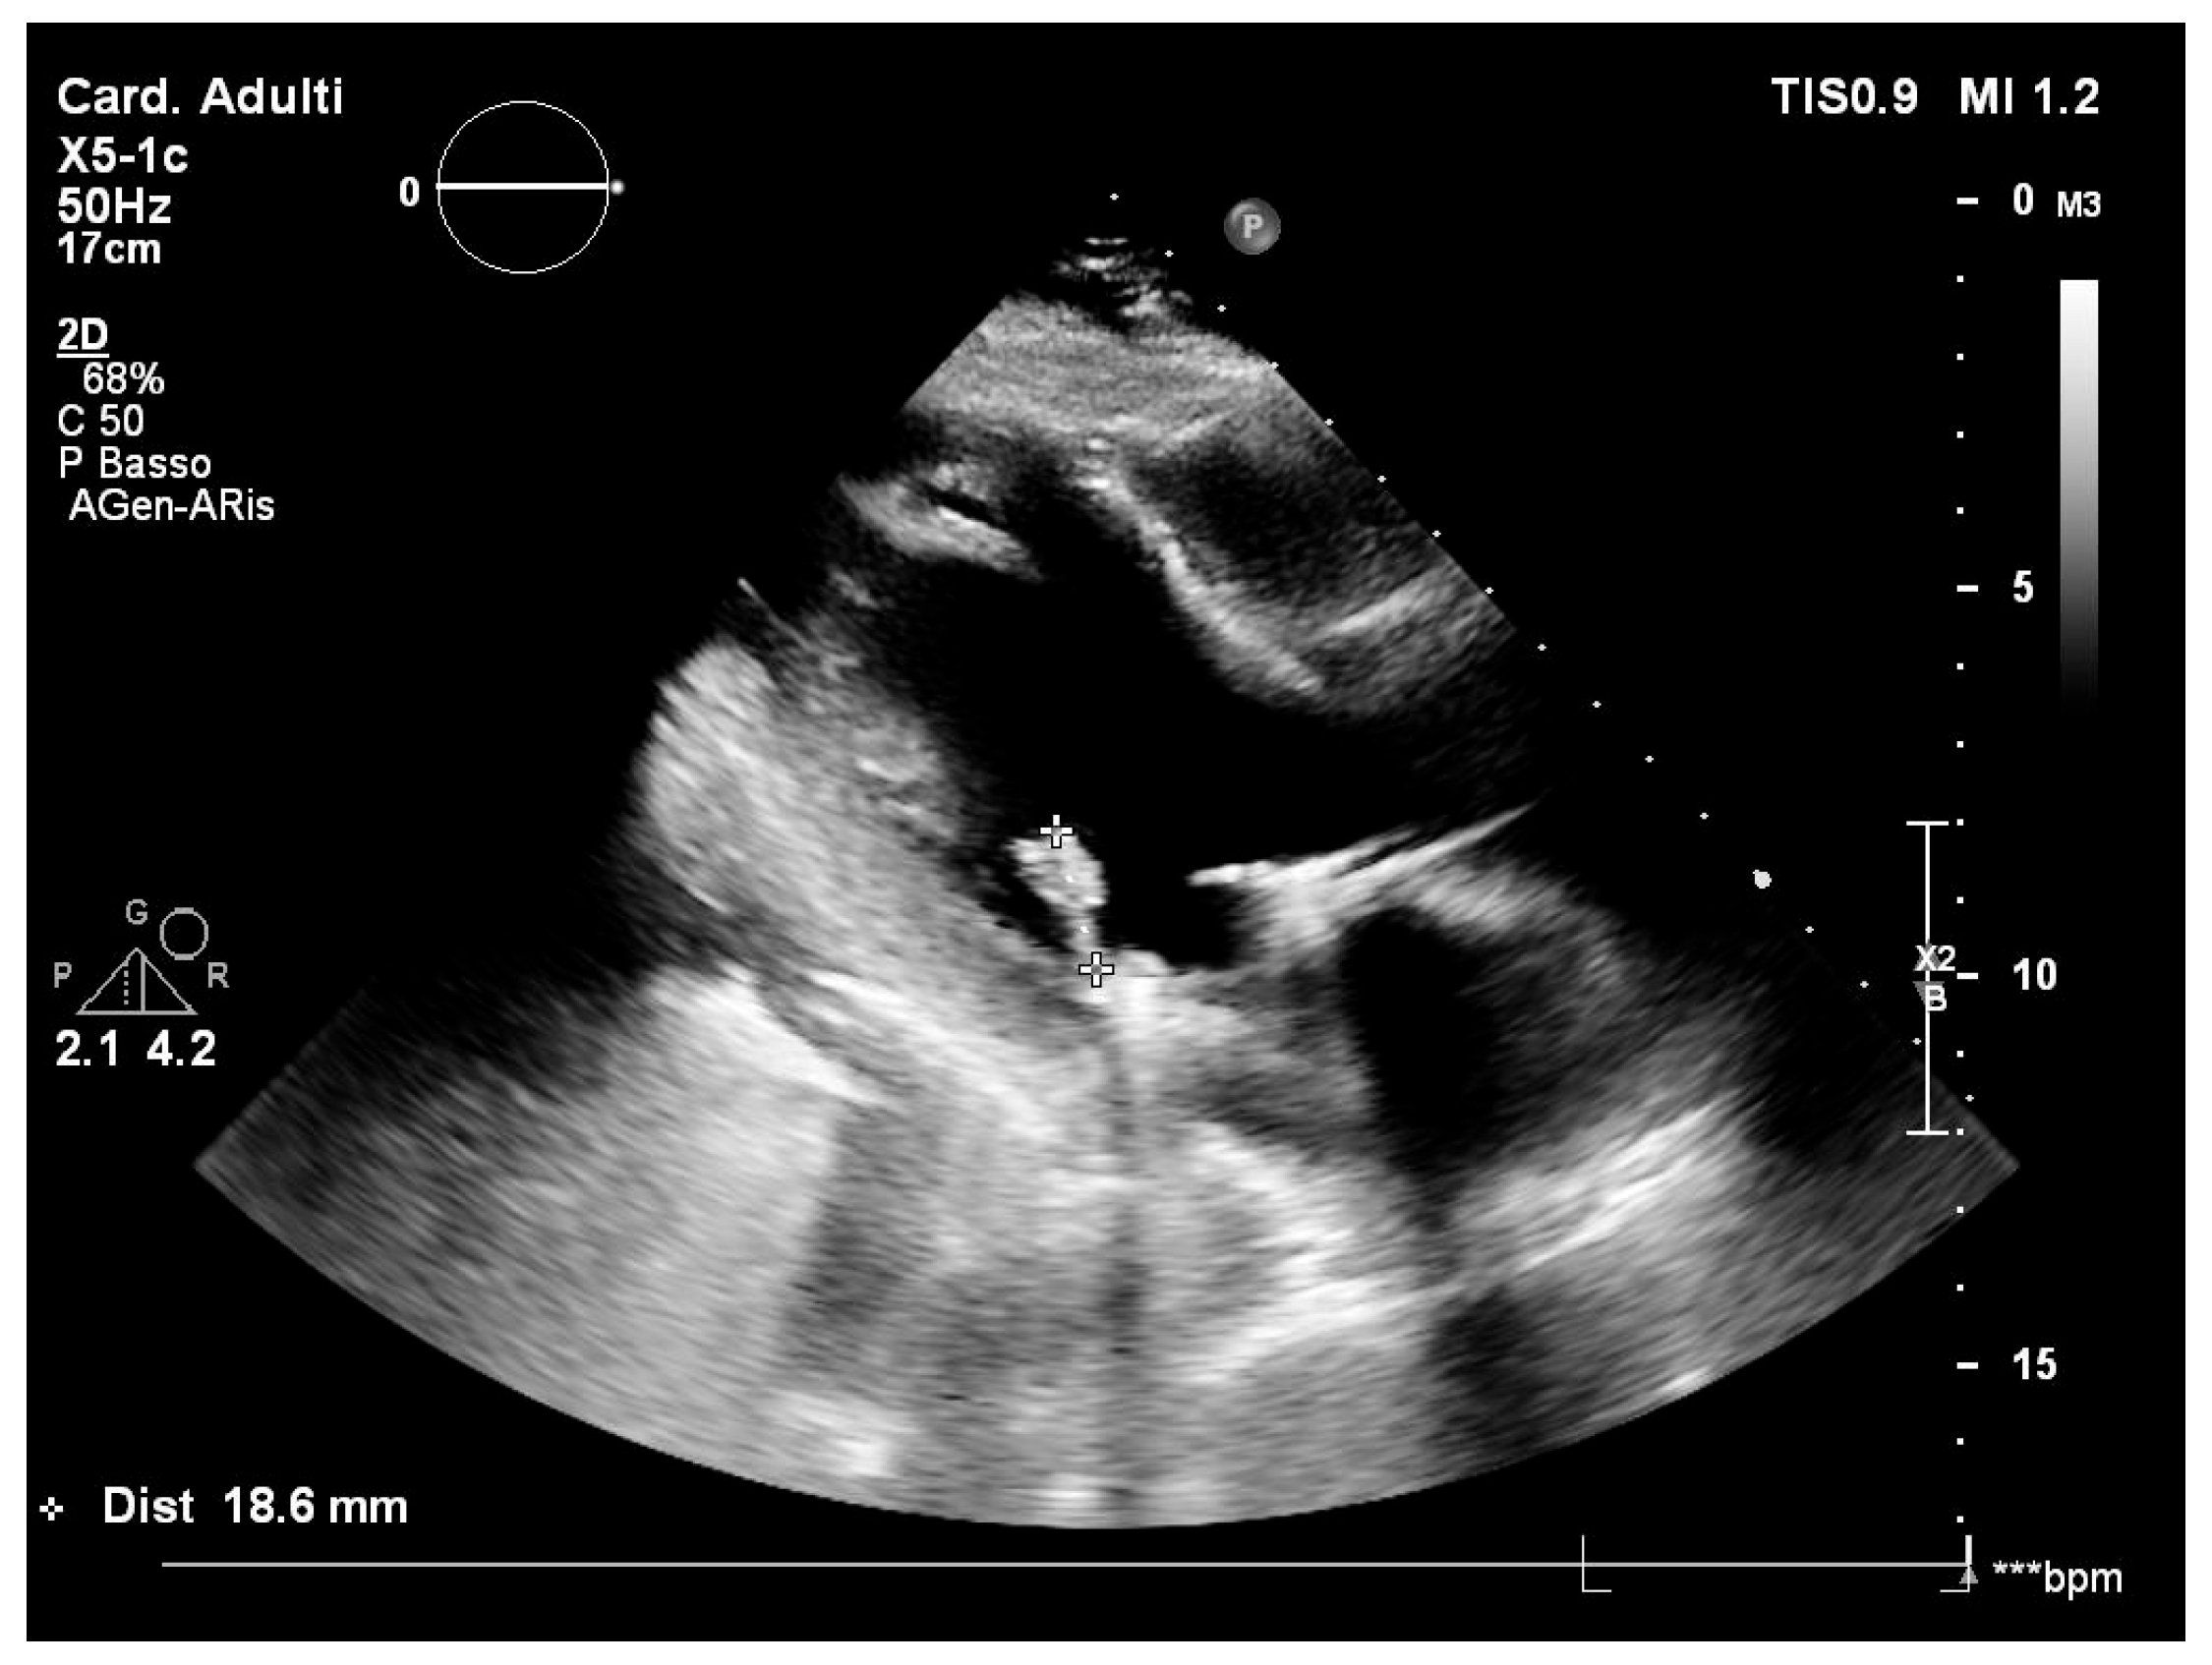

2. Case Report